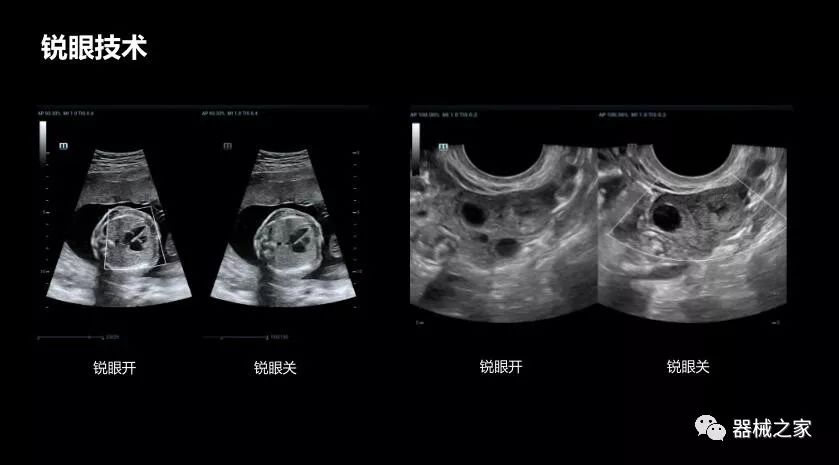

• 銳眼技術(shù)

做胎兒心臟檢查的時候,如果是聲窗不好的孕婦,很難看清胎兒心腔 。女媧Resona 8的銳眼技術(shù)能很好的優(yōu)化心腔內(nèi)的噪聲,讓胎心結(jié)構(gòu)完美的呈現(xiàn)。